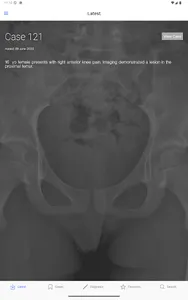

BoSTT brings the user a real experience of frequent and rare, typical and more unusual cases of bone and soft tissue tumours. Each case has a clinical history, high resolution radiology and pathology images, diagnosis, treatment and learning points.